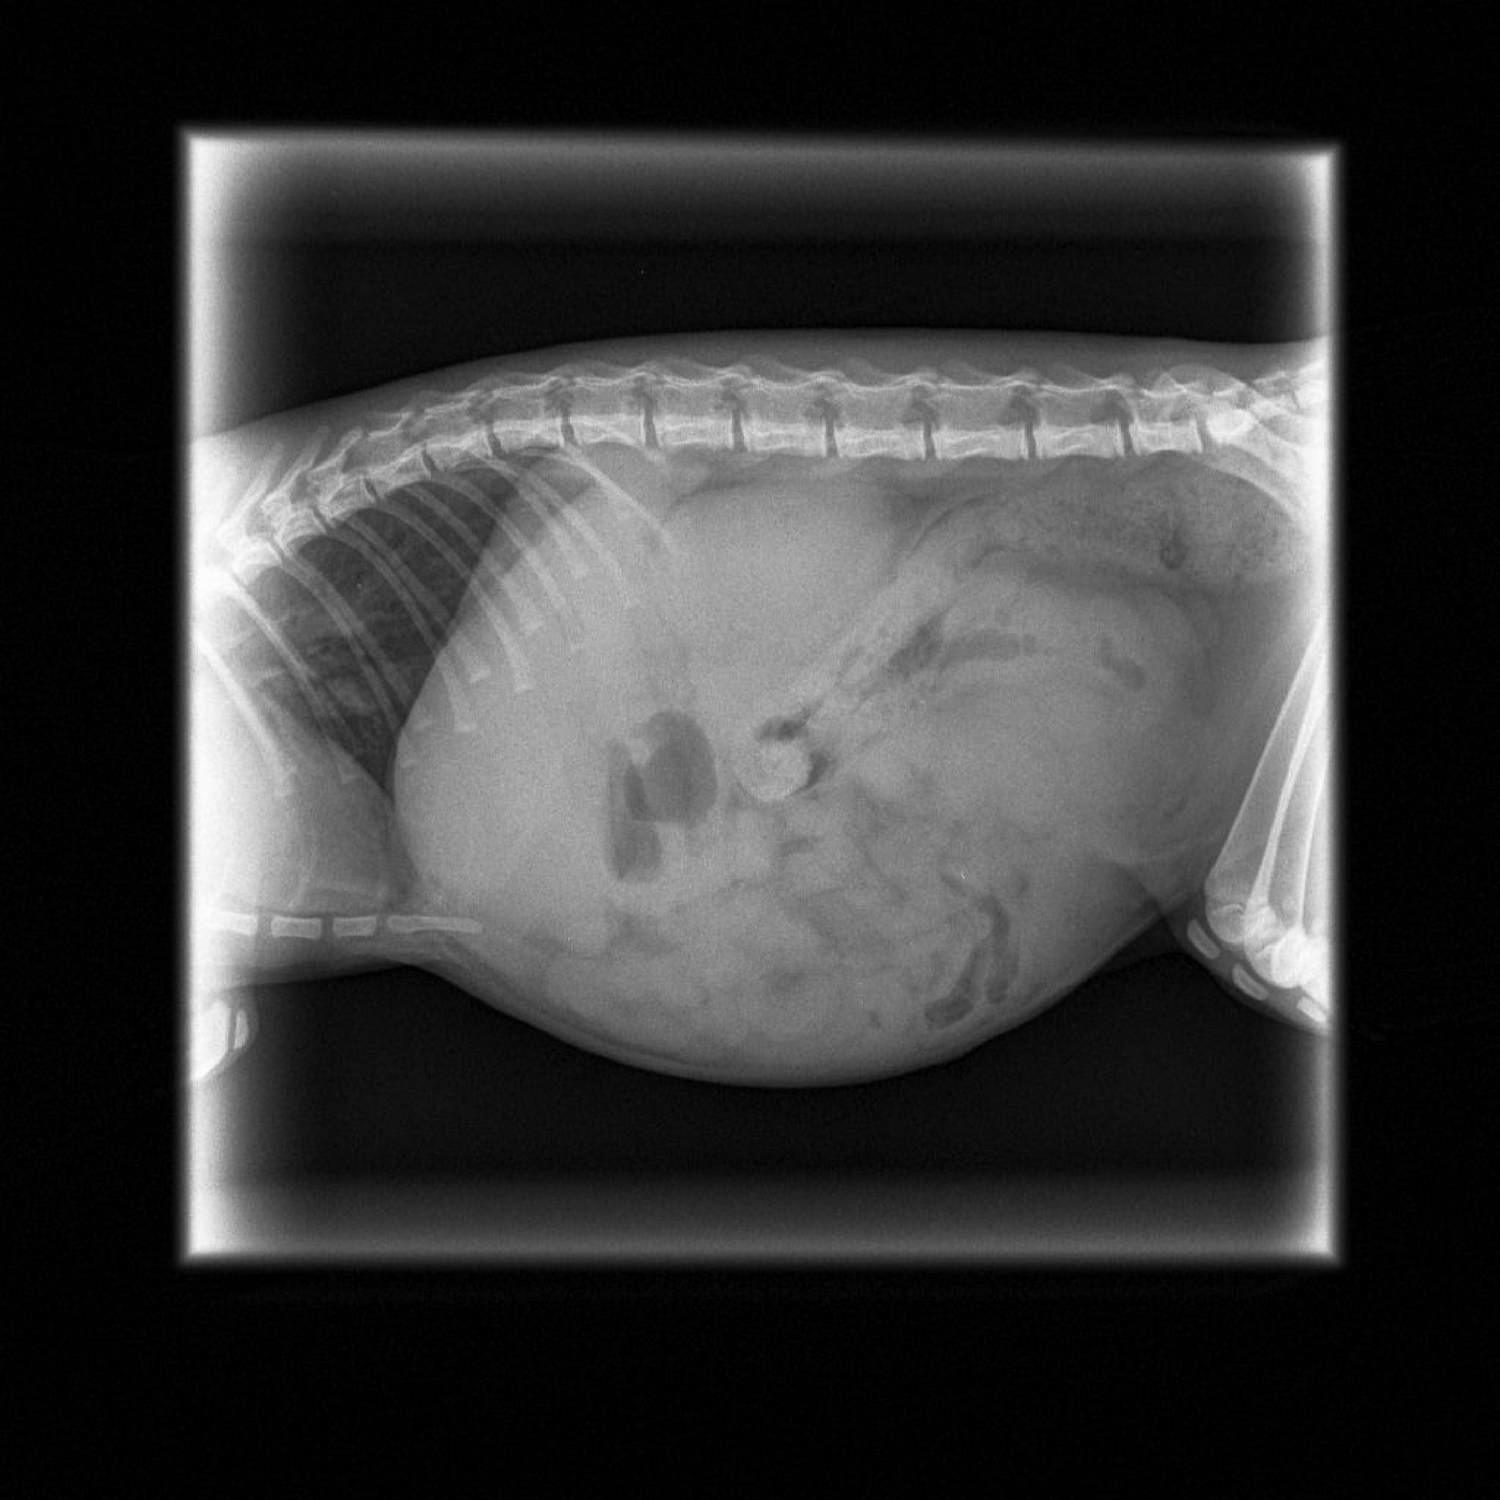

Cat Abdominal X Ray . Its a rubber band in the cats small intestine that is literally coming out of its fanny. Can you see all of the kittens in this. To examine bones and joints. Abdominal radiographs can show an intestinal obstruction, the size and health of the liver, spleen, and kidneys, find bladder stones,. The lungs and many joints. To look for problems with the organs and space in the abdomen, including the kidneys, liver, intestines, bladder, and uterus. Can you tell what the arrows are pointing to in the abdomen of this cat? Details of internal structures, such as the inner structure of the heart, the bladder, and other abdominal organs.

XRay image of obese cat with complete intestinal obstruction Cat Abdominal X Ray Can you see all of the kittens in this. The lungs and many joints. To examine bones and joints. Details of internal structures, such as the inner structure of the heart, the bladder, and other abdominal organs. Can you tell what the arrows are pointing to in the abdomen of this cat? To look for problems with the organs and. Cat Abdominal X Ray.